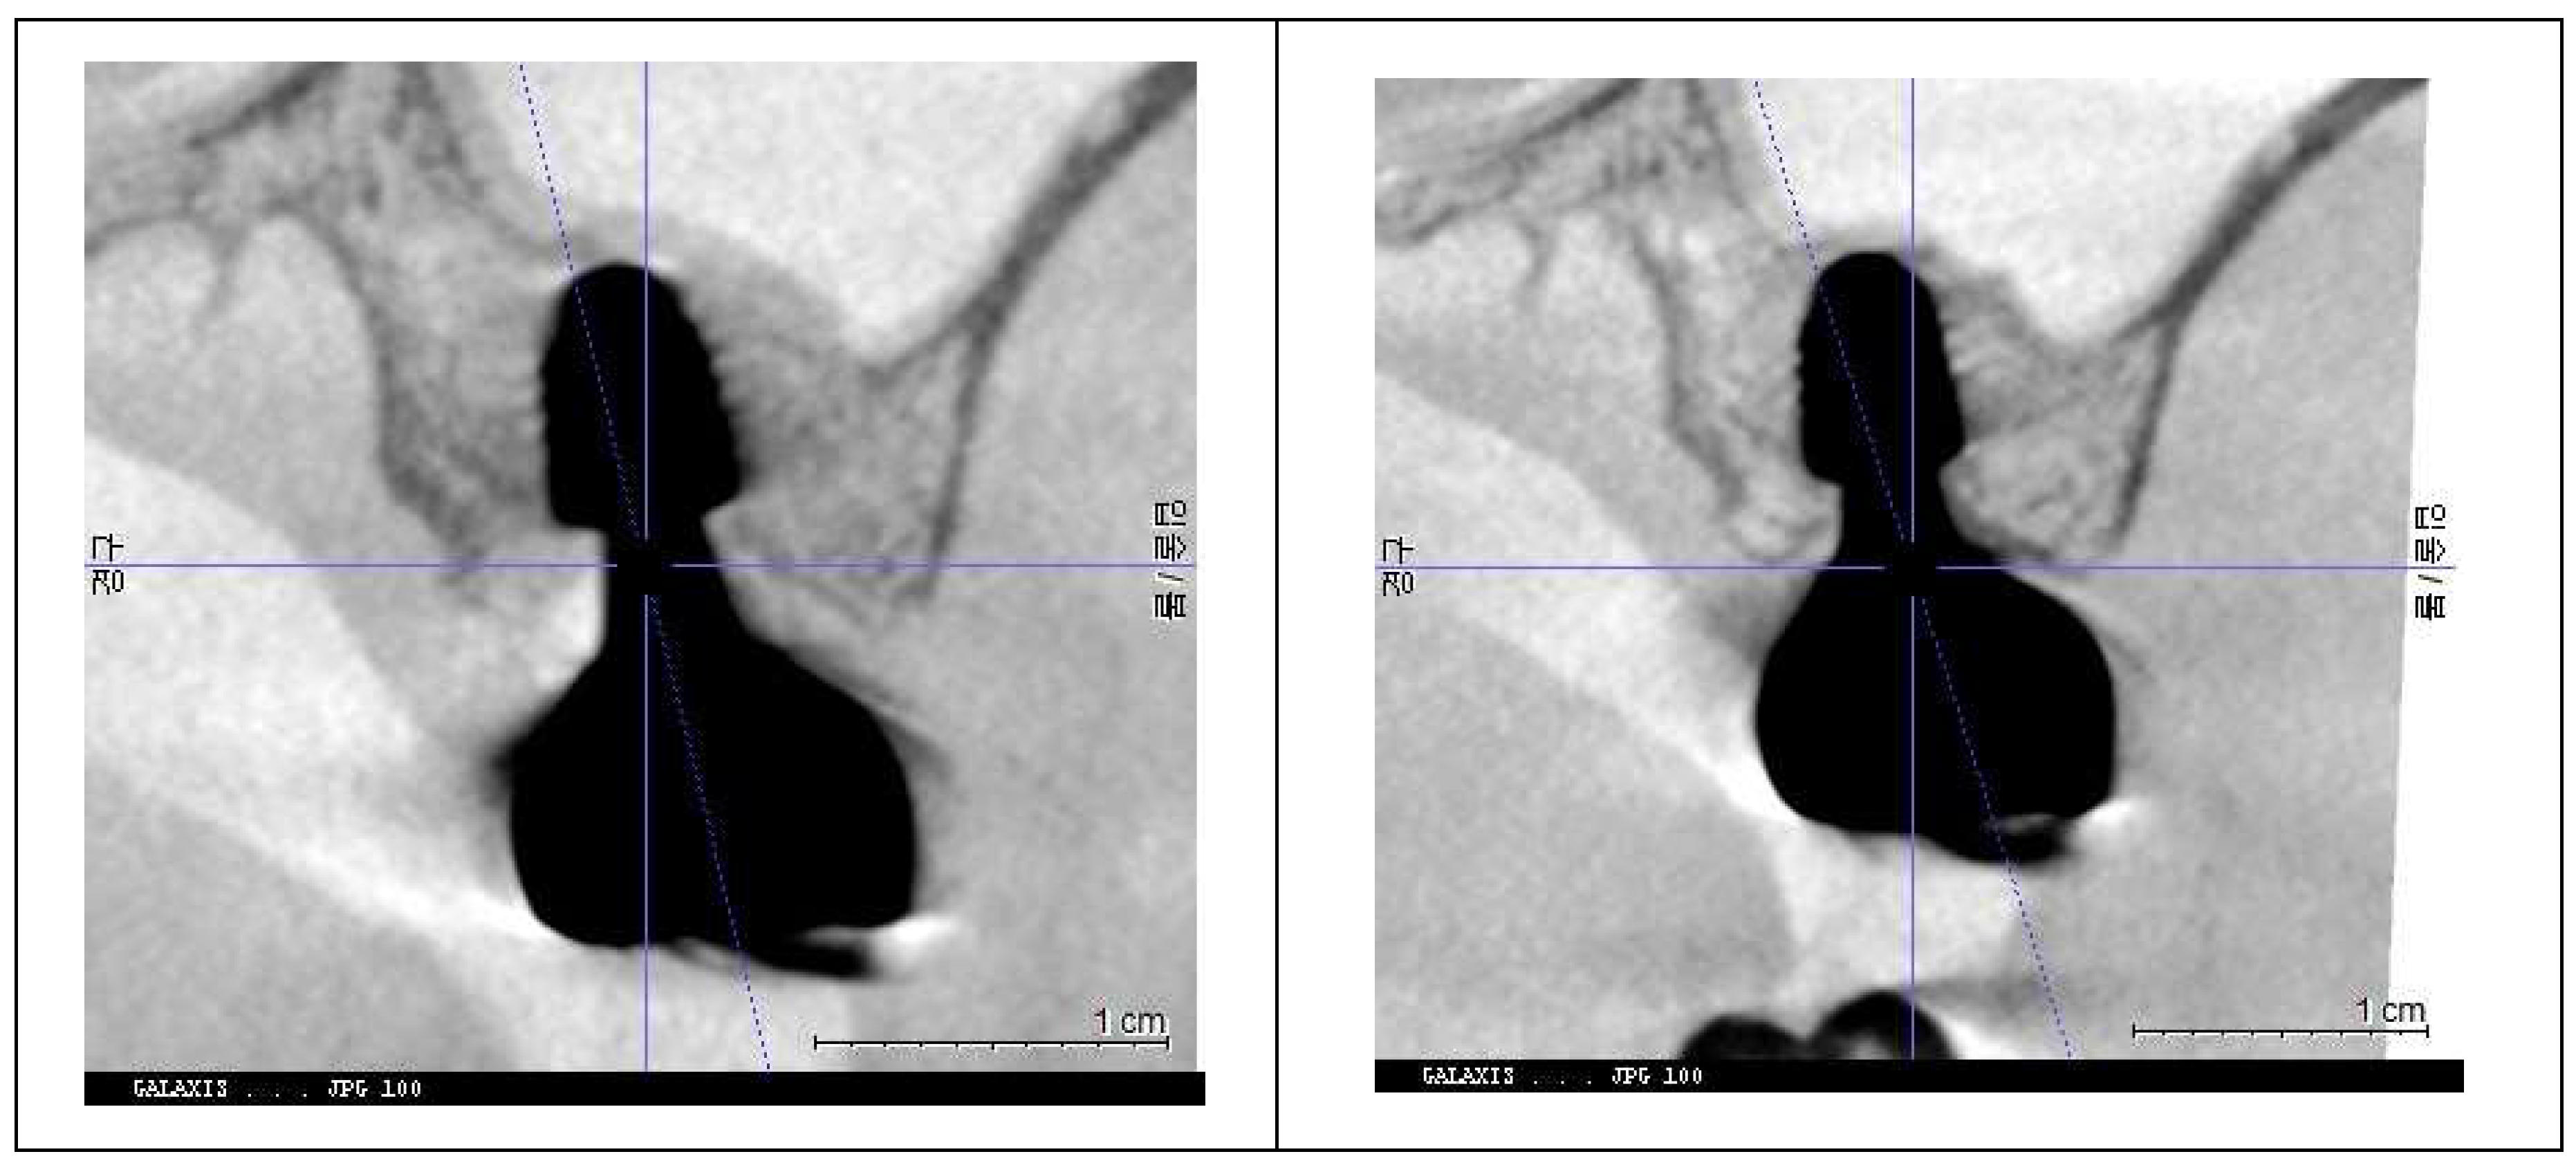

The two implant sites were analyzed in a split-mouth study using CBCT scans from 2021 and 2024 to assess peri-implant soft tissue and bone structure. CRD and DP measurements were obtained through CBCT imaging and clinical evaluations to examine their correlation with peri-implant health, particularly in managing peri-implant mucositis.

CRD and DP measurements for the upper left and lower right first molar implants were recorded in 2021 and 2024. Averages were calculated and compared over time, with results summarized in

-

B.

TreatmenT site (the upper left 1st molar) for peri-implant mucositis

- a)

Changes of CRD

Table 6.

Changes in CRD from 2021 to 2024 at the peripheral and central areas for the treatment site (the upper left first molar implant).

| pCRD |

2021 |

2024 |

changes |

| M |

1.91 |

0.58 |

-1.33 |

| D |

1.87 |

1.2 |

-0.67 |

| B |

2.04 |

0.76 |

-1.28 |

| L |

2.05 |

0.99 |

-1.06 |

| average |

1.97 |

0.88 |

-1.09 |

| cCRD |

1.52 |

0.62 |

-0.90 |

1.54 |

0.5 |

-1.04 |

1.88 |

-1.3 |

0.98 |

-0.48 |

1.48 |

0.55 |

-0.93 |

Figure 7 and

Figure 8 illustrate the radiographic changes observed from 2021 to 2024 at the lower right first molar implant site (control site) and the upper left first molar implant site (experimental site), respectively. (

Figure 7,

Figure 8.

This image illustrates the X-ray measurements conducted on the upper left first molar implant, comparing data from 2021 and 2024.